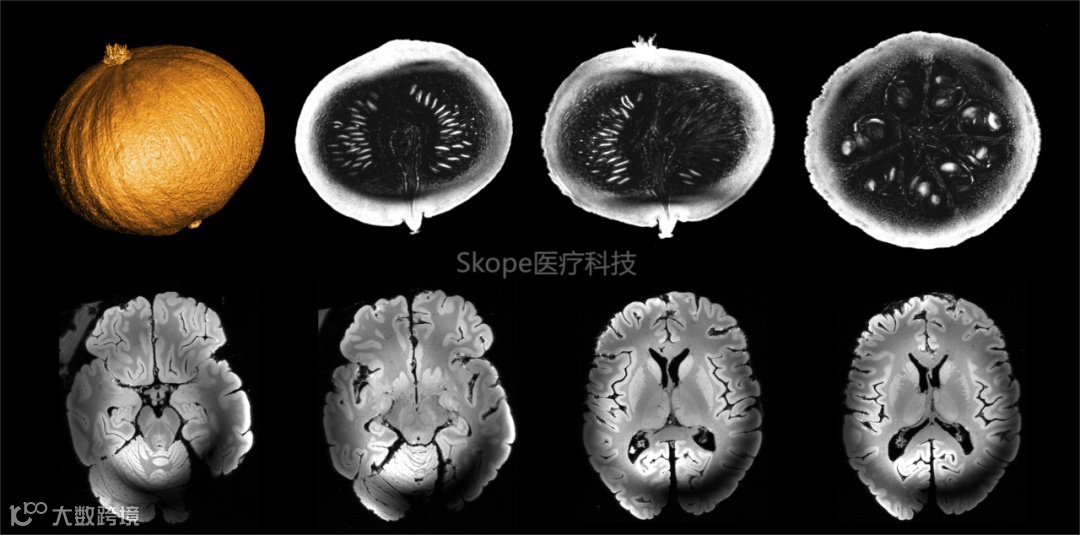

11.7T的首次扫描成像(南瓜与人脑标本) © AROMA